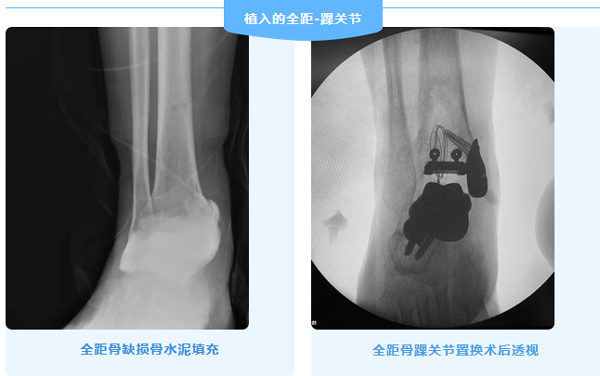

近日,北京积水潭医院足踝外科应用重建距骨以及3D打印全踝置换技术,成功为一名复杂全距骨缺如患者完成全踝关节置换术。

彭大叔回家乡等待消息的这两个月,足踝外科主任武勇与杜辉反复同工程师进行模拟推演,“如何完成如此复杂的全踝关节置换”成为摆在团队眼前的难题。对此,武勇主任指出这个病例的技术要点,第一,要将3D打印的距骨与跟骨,舟骨相关联,重塑围绕3D打印的距骨重建后足和中足;第二,要处理好缺如的内踝。经过团队多次探讨,反复三维模拟,最终确定了手术方案。

四月,彭大叔终于迎来了这场极其复杂的手术。在前期武勇主任的规划和设计下,手术当天,杜辉带着对彭大叔的承诺开始操作,术中克服重重困难,经过4个小时的努力,手术顺利的完成了!